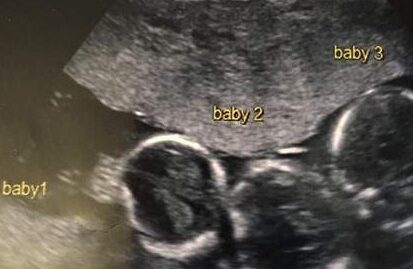

Early in her pregnancy, Becki-Jo experienced severe sickness and headaches. Because of this, her doctors scheduled an ultrasound a little earlier than usual — which is how they discovered she was expecting triplets.

The three boys — Rohan, Roman, and Rocco — were born via Cesarean section at 31 weeks, each weighing about 3 pounds 5 ounces. They spent their first six weeks in intensive care, building strength until they were ready to thrive on their own.